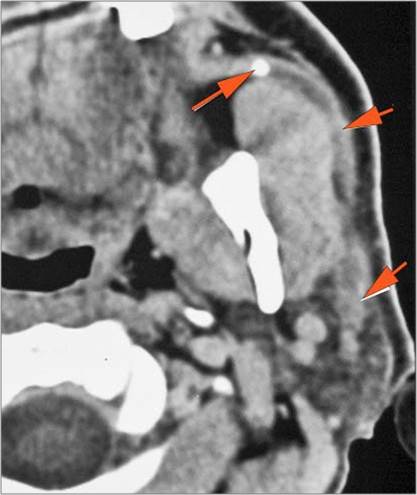

There is edema within the adjacent deep neck, retropharyngeal and/or prevertebral spaces

There is abscess within the adjacent deep neck, retropharyngeal and/or prevertebral spaces.

Prevertebral and Epidural Spaces

There is edema/abscess within in the prevertebral or paravertebral spaces.